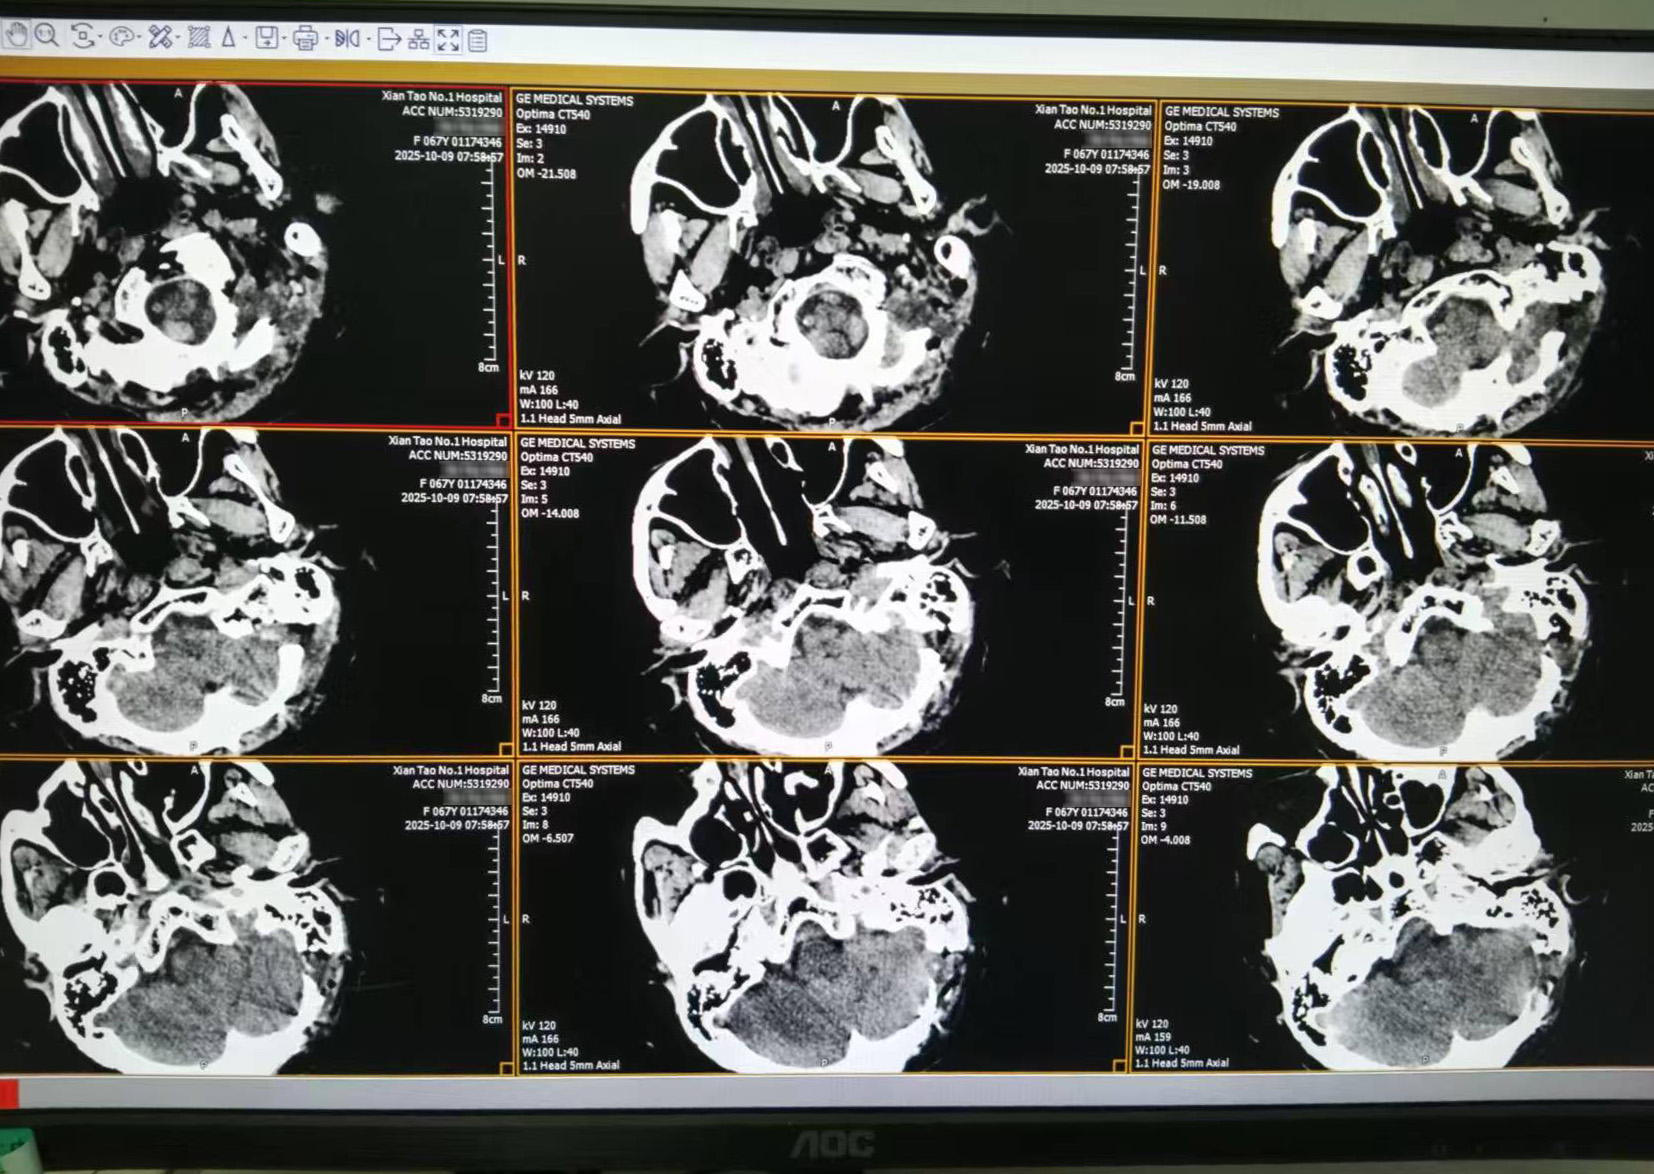

患者向女士(化名)一周前发现颅内肿物后入院治疗。经过颅脑MRI检查,显示其左侧桥小脑角区存在占位性病变,考虑听神经瘤可能。此时肿瘤已引发听力减退、头晕等明显症状。由于肿瘤位置深、紧邻重要神经血管,若不及时进行手术干预,患者将面临进行性听力丧失、面神经损伤等严重并发症的风险。

▲术后复查